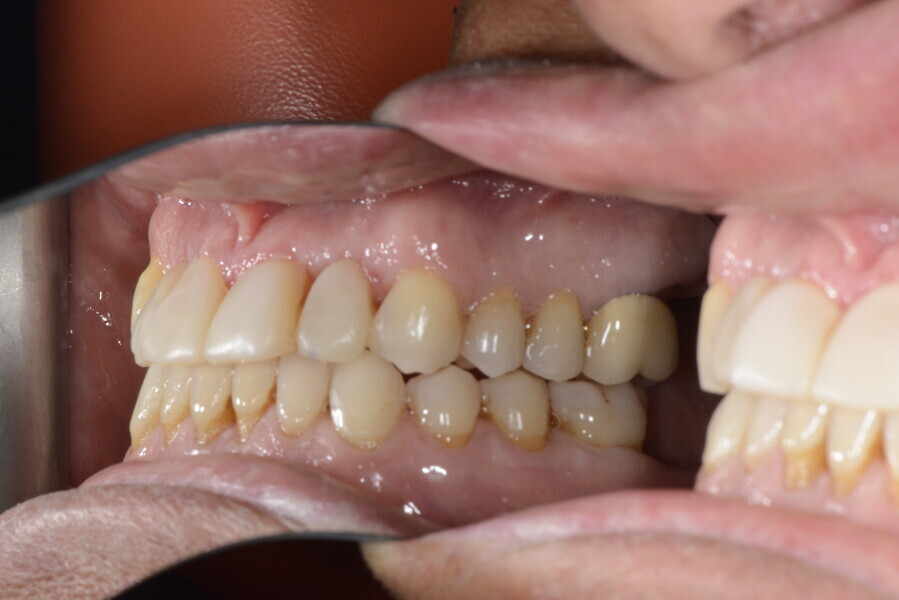

The 58-year-old patient wished to improve his oral aesthetics and function, complaining of mobility of the posterior teeth and wear of the anterior teeth. After data collection, a very complex situation was identified (Figs. 11–13):

1. severe periodontitis with poor prognosis of some teeth;

2. anterior crossbite;

3. severe wear mainly of the anterior teeth and compensatory eruption;38

4. atypical swallowing and lower posture of the tongue at rest;

5. masticatory dysfunction during the mastication test; and

6. no significant signs of temporomandibular disorder.

After the first phase of aligner treatment, we had achieved better inter-arch coherence, better maxillary arch expansion, and some space for improving the anterior tooth proportions restoratively (Fig. 19). We then temporarily restored the anterior teeth directly with composite, closing the spaces, improving the tooth proportions and further increasing the maxillary arch expansion (Fig. 20). We used restorative arch expansion to reduce the orthodontic destabilisation of the teeth to achieve the correct inter-arch coherence and retain the teeth in the cortical bone.38 A refinement aligner phase was undertaken to improve the final alignment of the gingival zenith and to improve the inter-arch coherence (Fig. 21). The periods of the first orthodontic phase and of the refinement were used to augment the mandibular and maxillary bone and to place the implants (Fig. 22). At the end of the orthodontic treatment, the case was finalised with ceramic veneers in the anterior area and temporary restorations on the implants in the posterior area (Figs. 23–26).